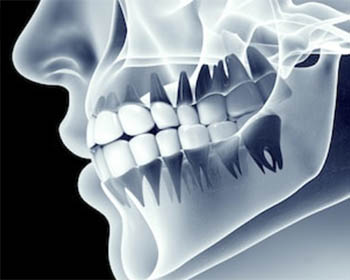

TAC CONE BEAM

La C.T. Cone Beam (CTCB) è il nuovissimo sistema di TAC dentale aperta, che ha rivoluzionato il mondo della radiologia digitale, è a basso dosaggio ed è utilizzata per la diagnosi delle patologie dell’apparato masticatorio, del distretto maxillo-mandibolare e nell’ambito otorinolaringoiatrico.

La C.T. Cone Beam, ha sostituito l’utilizzo della TAC tradizionale in Odontoiatria, poiché evidenzia le immagini con migliore definizione, e con una dose radiogena 20 volte inferiore, il tutto rigorosamente con la metodica di ricostruzione 3D.

L’esame dura in media, 13 secondi, il paziente non viene più posizionato all’interno di un’apparecchiatura a forma di tunnel, ma esegue l’esame in piedi, così potrà fare in studio, in pochi minuti, un esame che avrebbe potuto eseguire solo nei centri radiologici specializzati.

Per  questo vi è la possibilità per il Dottore e di avere in poco tempo un’esame 3D preciso e dettagliato, la risoluzione delle immagini è sub millimetrica e pertanto si possono fare valutazioni anatomiche estremamente precise, condizione essenziale per una diagnosi accurata ed efficace.

Un’altra caratteristica dell’esame è la possibilità di ottenere con un’unica scansione la ricostruzione di entrambe le arcate mascellari, superiore ed inferiore, senza costi ed esami aggiuntivi.

Oltre a ciò, tramite l’esame Cone Beam si possono visualizzare le strutture nervose (nervo alveolare inferiore), le vie aeree ed i seni paranasali.

Oggi l’esame T.C. Cone Beam rappresenta quindi il golden standard, degli esami radiologici in odontoiatria essendo un esame completo, dal costo contenuto, rapido nell’esecuzione e più rispettoso della biologia.